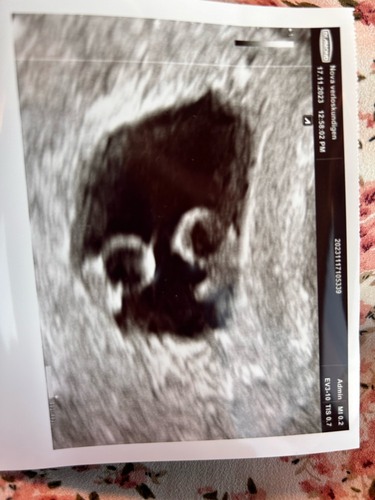

Hier ook 2 kloppende hartjes ❤️

Ben nu 8.1 weken.

Het moet in ons geval wel een eeneiige zijn want heb 1 cryo teruggeplaatst gekregen 😊

Het lijkt wel dat onze kleintjes een eigen zakje hebben. Nu nog spannend of ze ook de grote vruchtzak zelf hebben of die wel delen. En de placenta uiteraard. Op 4 dec weer een echo dus hopelijk zien we dan meer.